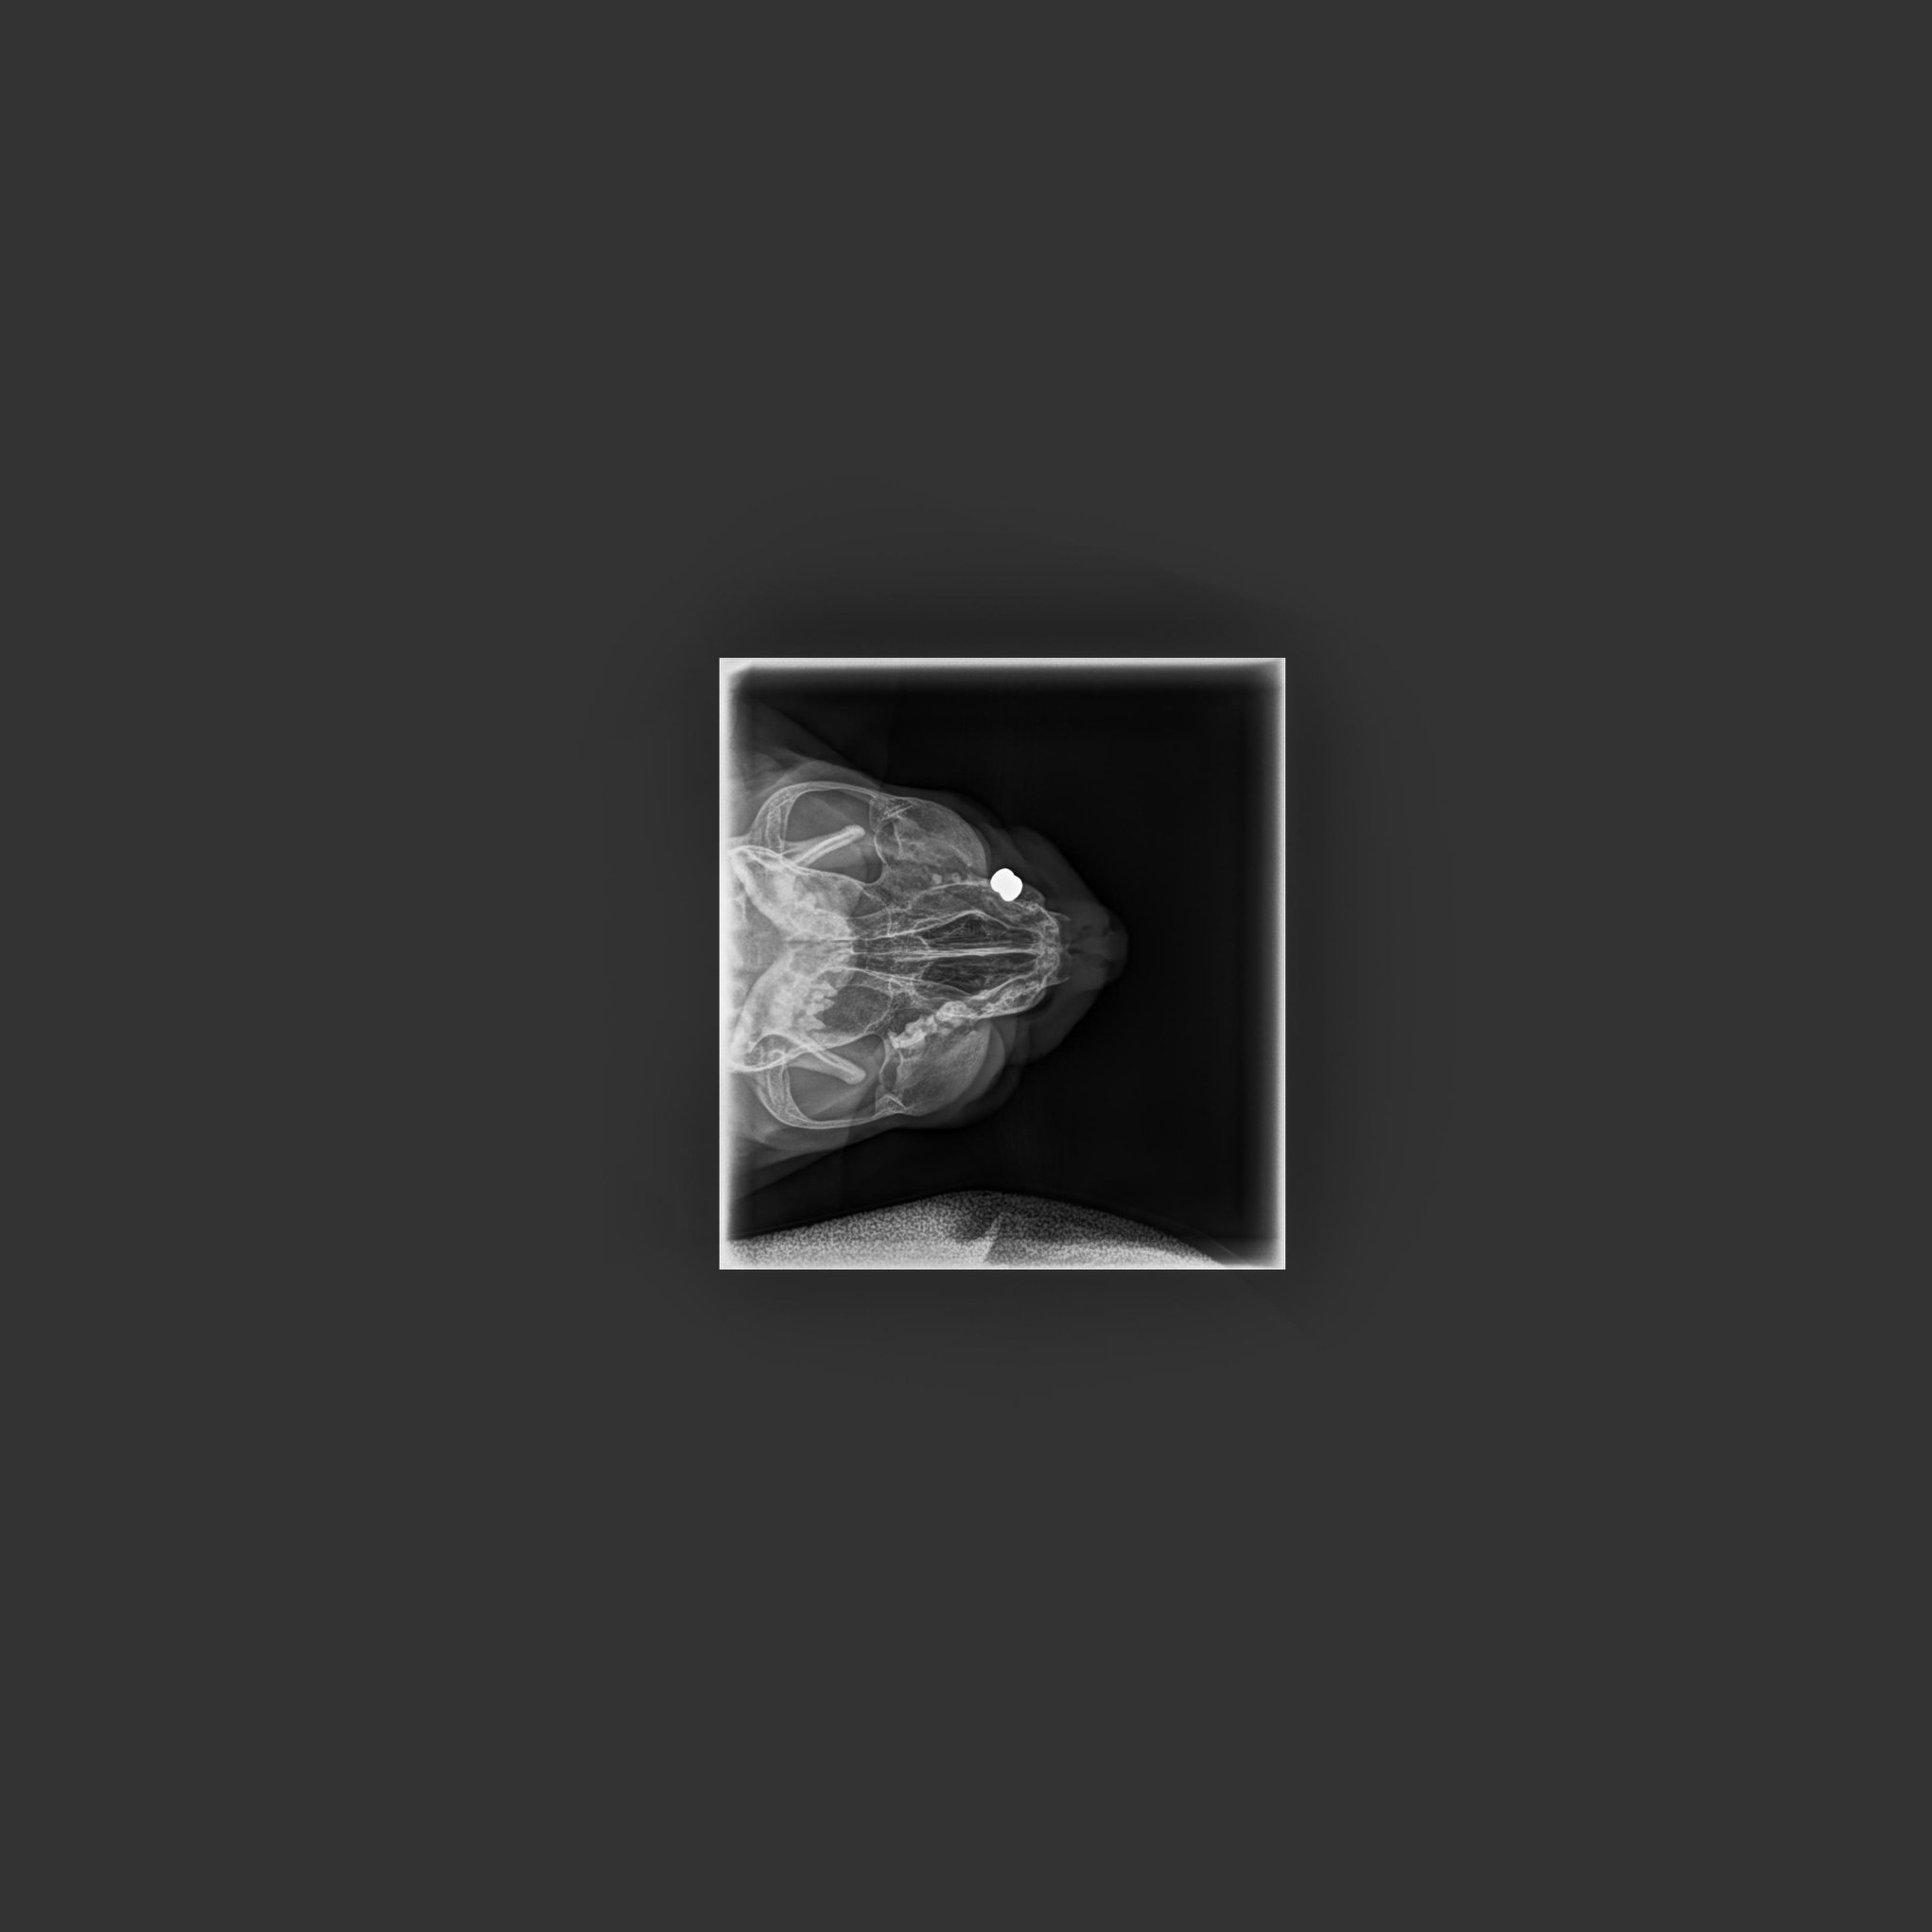

🔶Poslední týdny se rýma Šmudlovi zhoršila a tak se přistoupilo k vyšetření, k rhinoskopii. Ukázalo se, že příčinou je diabolka, která způsobuje Šmudlovi velké obtíže. Bohužel je však umístěna za kostí, ta se díky olovu rozpadá, ale diabolku nelze nijak vyndat. Diabolek má Šmudla v tělíčku i s touto osm. Kvůli tomu musí chudák Šmudla trpět..